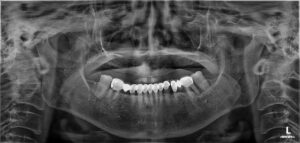

환자분께서 처음 본 원에

내원해 주셨을 당시 사진입니다.

사진을 보시게 되면 아래쪽 앞니가

브릿지로 연결되어 있는 것을 보실 수 있는데요.

연결된 보철물 중 오른쪽 큰 어금니가

흔들림이 있어 X-ray 촬영을 해보았더니

뿌리가 파절되어 있었고,

옆의 작은 어금니에도 시린 증상을 호소하셨습니다.

왼쪽 큰 어금니도 염증이 발생하여

잇몸뼈가 상당 부분 소실되어 발치가

필요한 상황이었습니다.